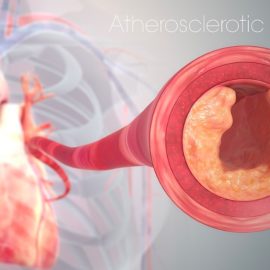

He also throws light on the harmful impacts of over-breathing, blocking effective oxygen distribution in the body due to subsequent carbon dioxide loss, leading to blood vessel narrowing and oxygen retention by red blood cells.

Proper breathing is a fundamental aspect of our overall wellness, yet it is often overlooked or misunderstood. In a recent podcast, the importance of proper breathing was discussed, shedding light on the misconceptions surrounding breathing and highlighting the benefits of nasal breathing. To fully grasp the significance of proper breathing, it is essential to understand some background knowledge. Mouth-breathing, for instance, refers to breathing through the mouth instead of the nose. This practice can lead to various health issues and hinder optimal oxygen intake. Another misconception is vertical breathing, which focuses solely on belly movements during respiration rather than considering the expansion and contraction of the lower rib cage.

The podcast emphasized that nasal breathing plays a crucial role in maintaining emotional equilibrium and mitigating stress. Nasal breathing allows for efficient filtration and humidification of air before it reaches our lungs, promoting better oxygenation and reducing potential irritants or allergens from entering our respiratory system. Additionally, nasal breaths help regulate carbon dioxide (CO2) levels in our bodies—a gas produced by metabolism—ensuring proper pH balance in our bloodstream.